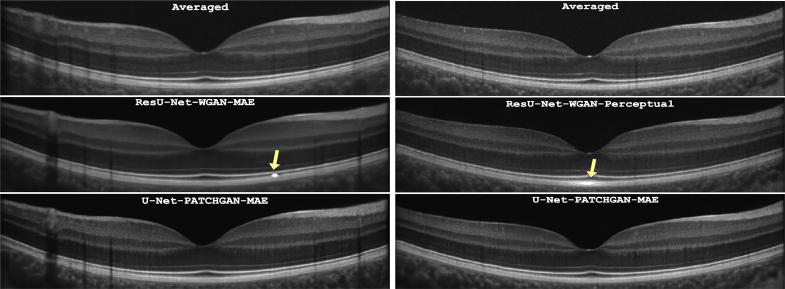

OCT is a widely used clinical ophthalmic imaging technique, but the presence of speckle noise can obscure important pathological features and hinder accurate segmentation. This paper presents a novel method for denoising optical coherence tomography (OCT) images using a combination of texture loss and generative adversarial networks (GANs). Previous approaches have integrated deep learning techniques, starting with denoising Convolutional Neural Networks (CNNs) that employed pixel-wise losses. While effective in reducing noise, these methods often introduced a blurring effect in the denoised OCT images. To address this, perceptual losses were introduced, improving denoising performance and overall image quality. Building on these advancements, our research focuses on designing an image reconstruction GAN that generates OCT images with textural similarity to the gold standard, the averaged OCT image. We utilize the PatchGAN discriminator approach as a texture loss to enhance the quality of the reconstructed OCT images. We also compare the performance of UNet and ResNet as generators in the conditional GAN (cGAN) setting, as well as compare PatchGAN with the Wasserstein GAN. Using real clinical foveal-centered OCT retinal scans of children with normal vision, our experiments demonstrate that the combination of PatchGAN and UNet achieves superior performance (PSNR = 32.50) compared to recently proposed methods such as SiameseGAN (PSNR = 31.02). Qualitative experiments involving six masked clinical ophthalmologists also favor the reconstructed OCT images with PatchGAN texture loss. In summary, this paper introduces a novel method for denoising OCT images by incorporating texture loss within a GAN framework. The proposed approach outperforms existing methods and is well-received by clinical experts, offering promising advancements in OCT image reconstruction and facilitating accurate clinical interpretation.